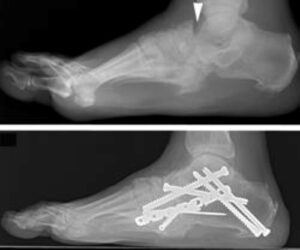

- X-rays: X-rays are a crucial diagnostic tool for Charcot foot. In the early stages, X-rays may appear normal. However, as the condition advances, signs such as fractures, bone fragments, and joint destruction become evident. Over time, more severe deformities, dislocations, and new bone formations may develop, indicating progressive Charcot arthropathy.